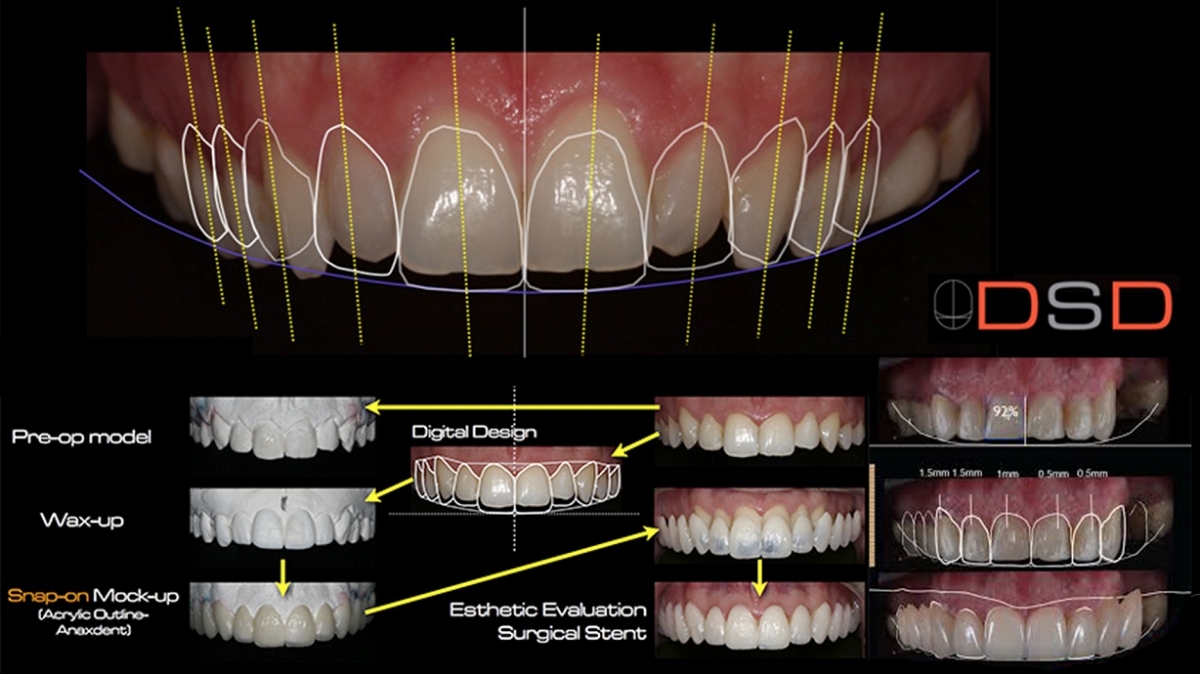

Digital Smile Design DSD Using Microsoft PowerPoint Full Protocol

DSD Digital Smile Design Online Presentation

Another Digital Smile Design Powerpoint Template you can download

- Implant CE Article Digital Smile Design In Implant Dentistry

- DSD Digital Smile Design Online Presentation